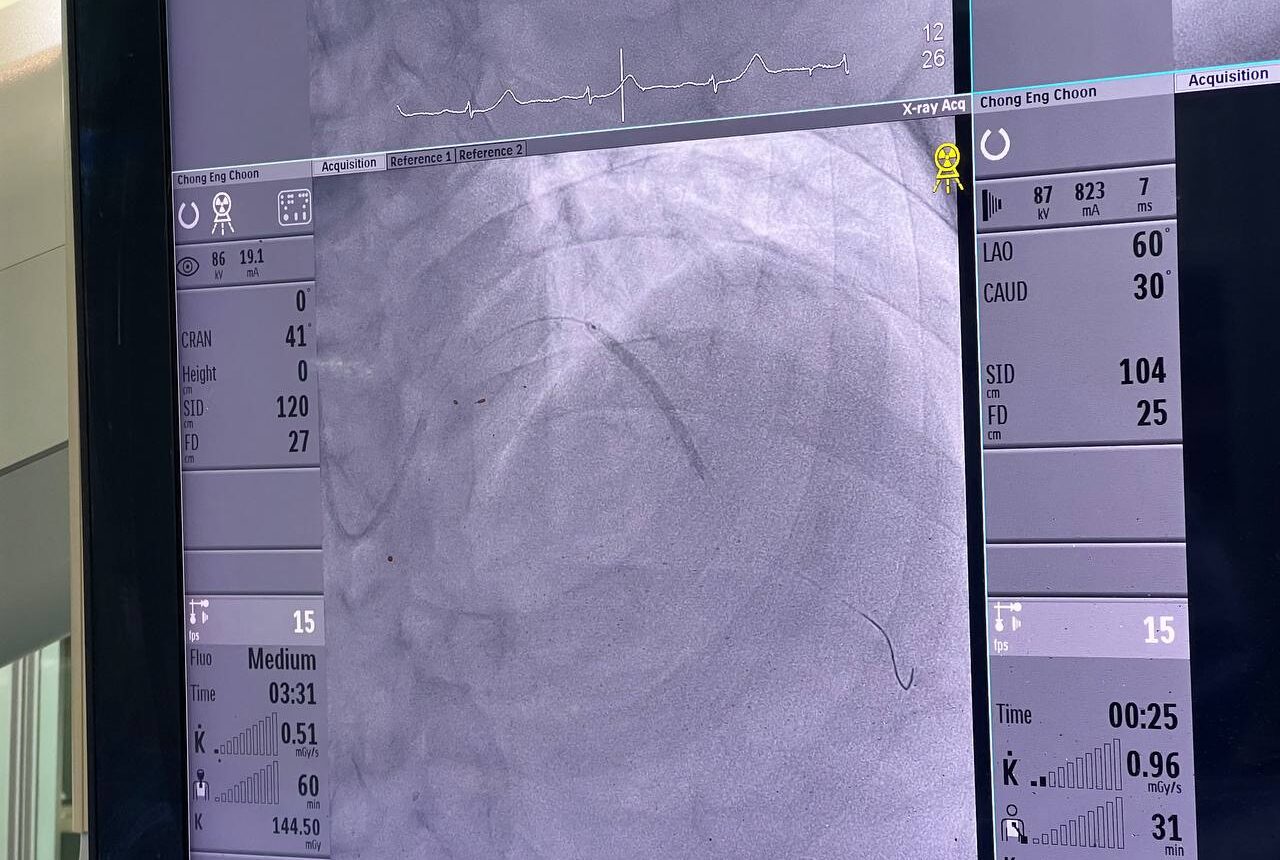

The first patient, with an inferior myocardial infarction, received primary PCI within an impressive 51 minutes, setting a remarkable precedent for efficient and effective care.